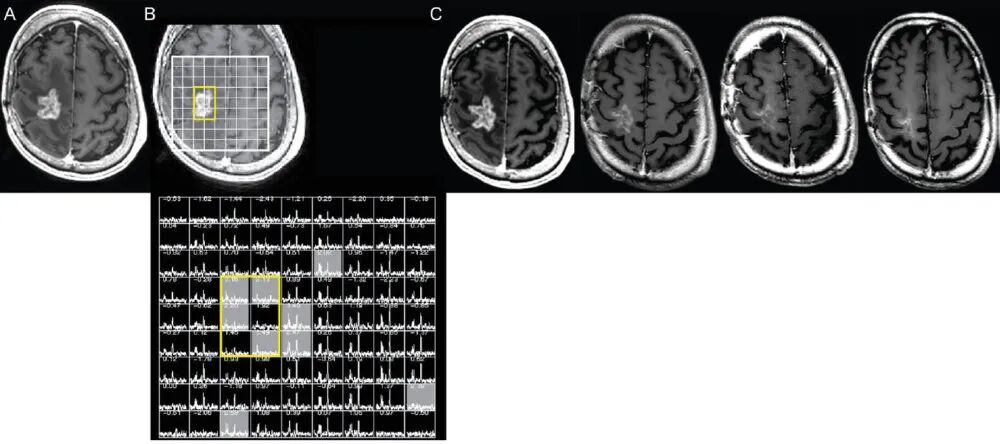

以下是MRS图例。

假性进展与真实进展在胶质母细胞瘤中的区别:神经外科医生需要了解的内容。J Neurosurg. 2023年9月1日;139(3): 748-759,第752页。

图A显示了对比后影像上的增强块。图B展示了覆盖在多体素波谱图上的网格,黄色区域位于增强块的中心。图B下方的网格显示,在正常脑组织区域(黄色框外)有NAA和胆碱峰,但在增强肿块区域没有NAA峰和胆碱峰。NAA和胆碱的减少与假性进展一致,因为在肿瘤中,你会期待看到胆碱峰升高和NAA峰降低。图C中的随访扫描显示,八个月内增强区域减少,这与MRS预测的假性进展一致。